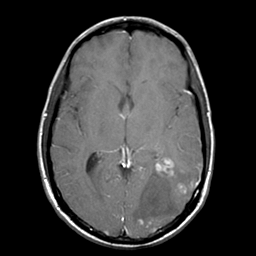

Sarcoma, MR Study #1 mr-gad -- Slice #11

[Home][Help][Clinical] Slice 11